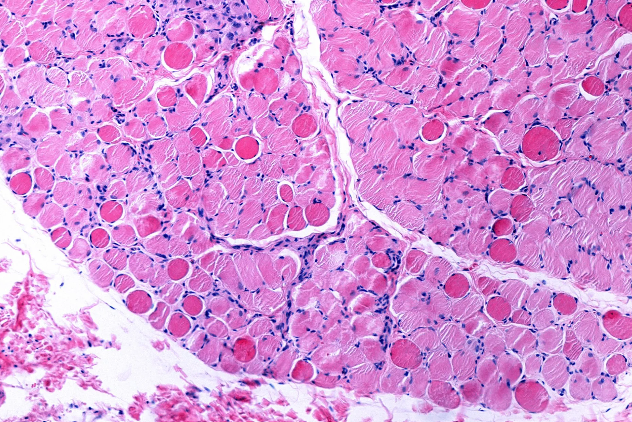

Slide of cells with Duchenne/ Becker Muscular Dystrophy

Duchenne and Becker muscular dystrophies are rare, genetically inherited neuromuscular disorders that lead to progressive muscle weakness and degeneration, profoundly affecting individuals and families across the world. At the heart of both conditions is a mutation in the DMD gene, which provides instructions for making and regulating dystrophin, a protein essential for stabilizing and protecting muscle fibers during movement and everyday activity. In Duchenne muscular dystrophy (DMD), mutations typically prevent the body from producing functional dystrophin, causing symptoms to emerge in early childhood and leading to loss of ambulation and serious complications involving respiratory and cardiac function over time. In contrast, Becker muscular dystrophy (BMD) results in the production of partially functional dystrophin, which usually leads to a later onset and slower progression of muscle weakness.